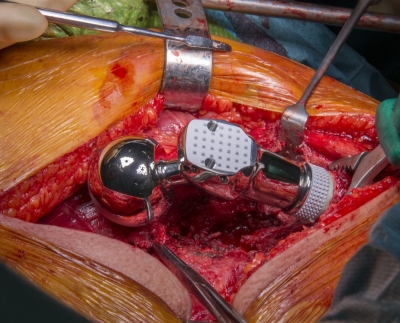

Jei laiku nesiimsite priemonių, tai baigiasi visišku sąnario praradimu. Ir vienintelė išeitis, kuri lieka — tai operacija sąnariui pakeisti dirbtiniu. Bet aš PRIMYGTINAI PRAŠAU iki to neprivesti. Sąnario keitimas ir pati chirurginė intervencija dažnai baigiasi infekcija, iki pat galūnės amputacijos!

Nuotraukos 18+

Sąnario pakeitimo dirbtiniu operacijos nuotrauka.Endoprotezavimas 60%-70% atvejų sukelia protezų atmetimą, kuris veda prie nepakeliamo lėtinio skausmo ir visiško galūnės funkcionalumo praradimo.